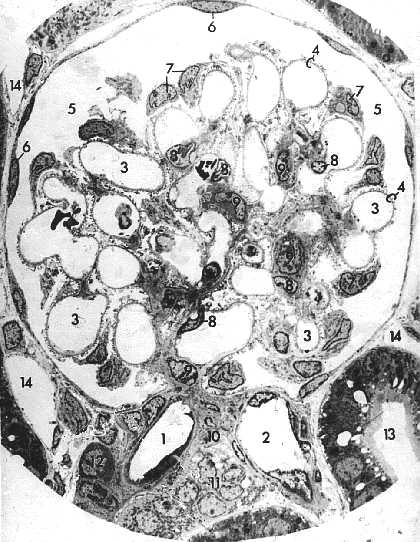

| Электронная микрофотография - почечное тельце. а) Наконец, наиболее полно компоненты почечного тельца выявляются под электронным микроскопом. б) Перечислим их в той же последовательности, как они были описаны в п. 28.2.3.1. | |

1. а) Сосуды:

приносящая артериола (1),

капилляры (3) клубочка

и их эндотелиоциты (8; отмечены ядросодержащие части клеток),

выносящая артериола (2).

б) Напомним, что участок почечного тельца, где входит приносящая и выходит выносящая артериолы иногда обозначается как его (тельца)

сосудистый полюс (10).

2. а) Капсула Шумлянского-Боумена:

париетальный листок (6) (образован однослойным плоским эпителием),

полость (5) капсулы.

висцеральный листок (7) (образован подоцитами; отмечены их выбухающие ядросодержащие тела);

б) Структуры, отделяющие просвет капилляров от полости капсулы, составляют

фильтрационный барьер (4).

3. Мезангиальные клетки (9; плохо видимая цифра - примерно в центре тельца).

4. Наконец, видны и некоторые образования, которые не входят в состав почечного тельца:

стенка дистального извитого канальца, прилегающая к почечному тельцу между двумя артериолами (самый низ снимка);

проксимальный извитой каналец (13) и капилляры канальцев (14).